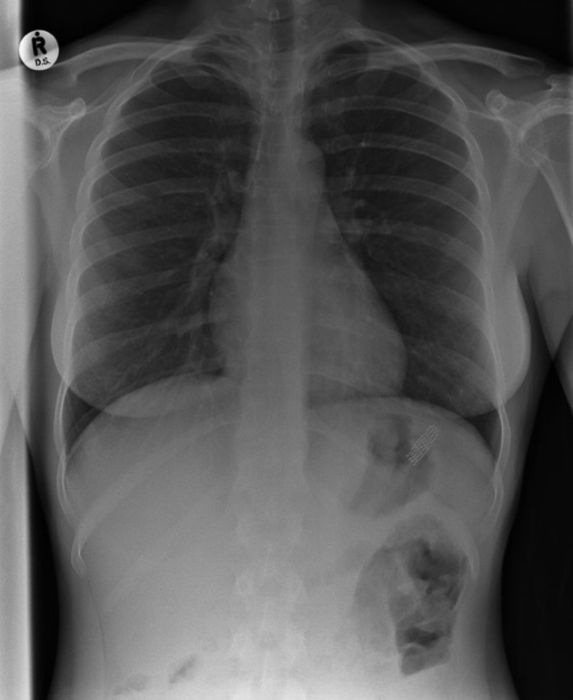

Жуткие рентгеновские снимки

Порой даже не верится, с какими странными и необычными повреждениями в травматологию могут поступить пострадавшие. Всю эпичность профессии врачей травматологии могут с легкостью подтвердить рентгеновские снимки. Просто жесть, да и только..